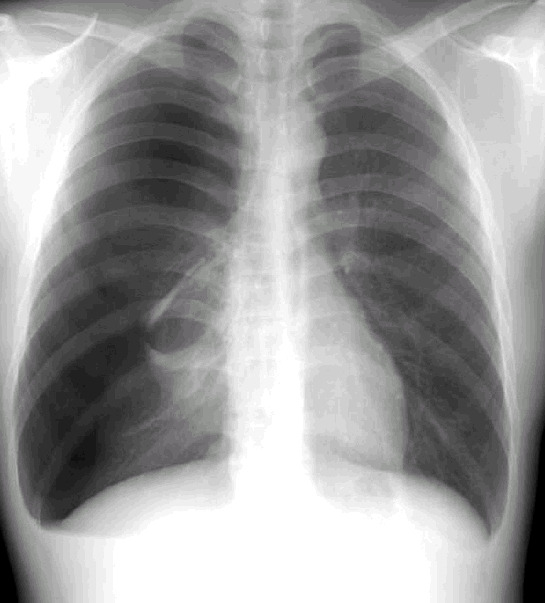

기흉은 흉부 X-ray나 CT 검사로 진단할 수 있습니다.

의사는 폐의 수축 정도를 보고 치료 방법을 결정합니다.

- 경도 기흉 (소량의 공기만 있음) → 자연 치유 가능

- 중등도 이상 기흉 → 공기를 빼내는 치료 필요

- 긴장성 기흉 → 응급상황, 즉시 흉관 삽입 필요

긴장성 기흉은 폐뿐만 아니라 심장까지 압박해 혈압이 급격히 떨어질 수 있는 생명 위협 상황이므로 즉각적인 응급조치가 필수입니다.